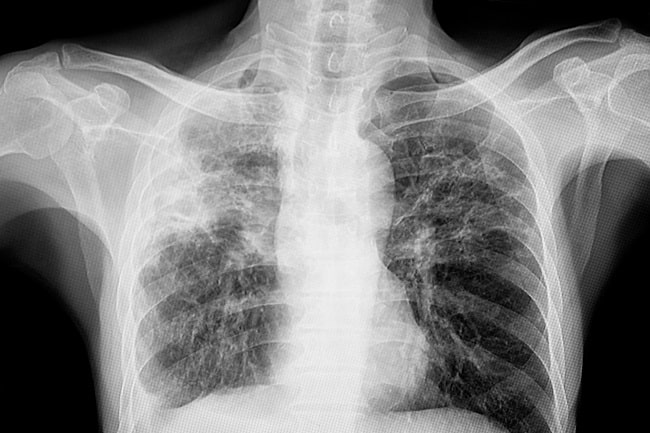

Untuk menegakkan diagnosis fibrosis paru, dokter biasanya akan melakukan serangkaian pemeriksaan. Pemeriksaan ini meliputi tes fungsi paru untuk menilai kapasitas pernapasan, foto rontgen dada, serta CT scan resolusi tinggi untuk melihat tingkat kerusakan jaringan paru. Dalam beberapa kasus, dokter juga dapat melakukan biopsi paru untuk memastikan diagnosis.